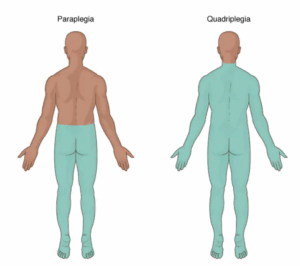

Spinal cord injury

A spinal cord injury involves damage to any part of the spinal cord. It also can include damage to nerves at the end of the spinal cord, known as the cauda equina.